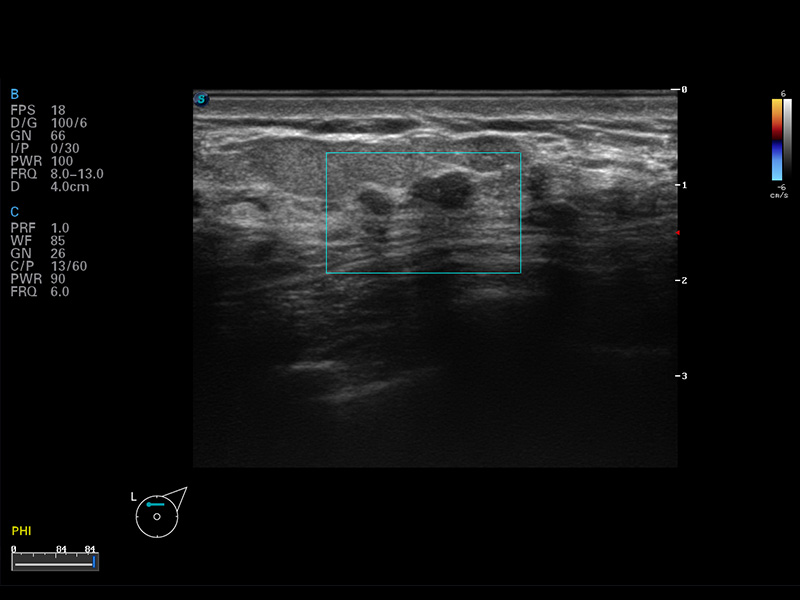

S8 EXP便携式彩色多普勒超声诊断仪是1xBET研发的高端全身应用型便携彩超。高通道的VIS平台融合可视化(Visual)、智能化(Intelligent)和人性化(Smart)的特点,配以1xBET自主研发生产的探头大家族,使您能够快速、准确的获得病人信息,提高工作效率的同时减轻疲劳。

μ-Scan微米成像

空间复合成像